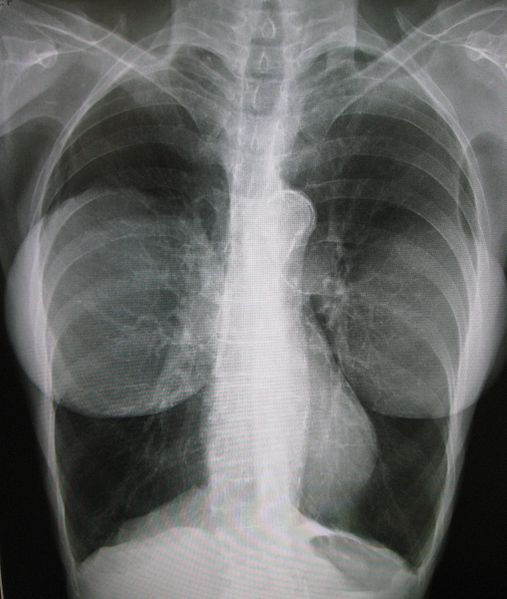

Chronic obstructive pulmonary disease

You may have heard of chronic obstructive pulmonary disease (COPD) referred to by the older terms “emphysema” (indicating particular kinds of lung changes) or “chronic bronchitis” (indicating particular symptoms including coughing up phlegm).

COPD is a lung disease most commonly caused by tobacco smoking or air pollution. In rare cases, a patient may suffer from COPD due to a genetic disorder.

In COPD, the normally spongy lungs become filled with large holes, or “bullae,” which makes the lungs appear even darker on a chest x-ray. Here’s an example of lung bulla (a hole or “blister”) circled in black, from a patient who has COPD due to the genetic disorder alpha-1 antitrypsin deficiency: